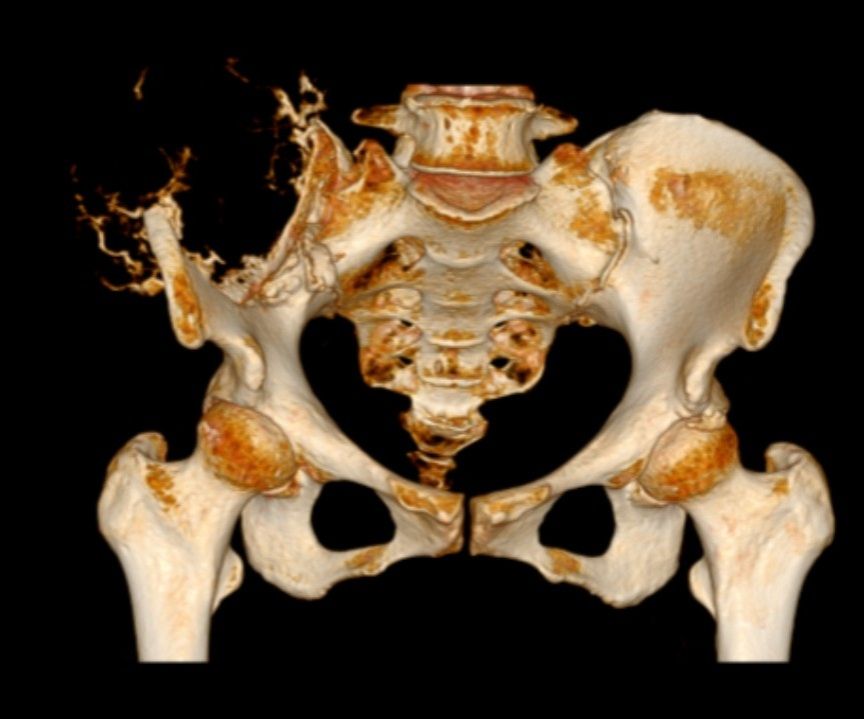

患者因持续加重的髋部疼痛、活动受限就医,经我院详细检查,确诊为骨盆巨大肿瘤。影像学显示,这个巨大占位不仅侵犯了右侧髂骨、部分骶骨及周围软组织,更紧密包绕了重要的血管神经丛。骨盆区域解剖结构异常复杂,血供丰富,神经密集,历来是外科手术的“高危雷区”。如此巨大的肿瘤,完整切除同时保护关键结构、控制致命性出血、维持骨盆稳定性的难度堪称“登峰造极”。

面对这一严峻挑战,我院迅速集结了脊柱骨肿瘤科、普通外科、血管外科、麻醉科、手术室、重症医学科、输血科、病理科及影像科的权威专家,成立专项治疗组。团队依托先进的3D打印技术,精准复制患者骨盆模型,进行手术模拟预演;利用术中神经电生理监测、先进的影像导航等尖端设备,为手术保驾护航;并制定了详尽的血管控制预案、大出血应对方案及骨盆功能重建策略。